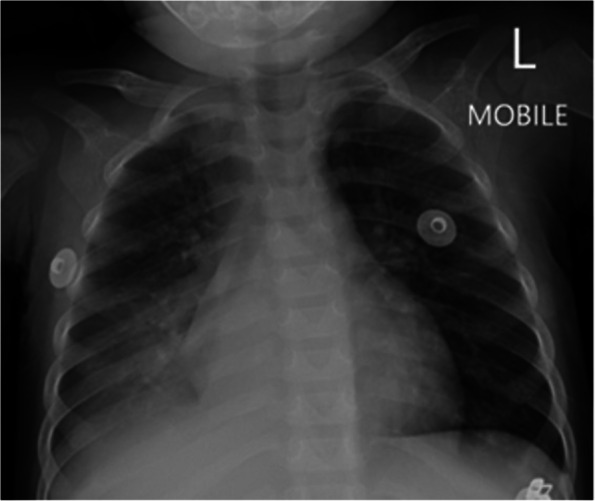

Fig. 4.

Case 2, chest radiograph on day 1 of admission. Chest radiograph (anterior–posterior projection) showing air-space consolidation in the right middle lobe and right lower lobe, with segmental atelectasis of the right upper lobe